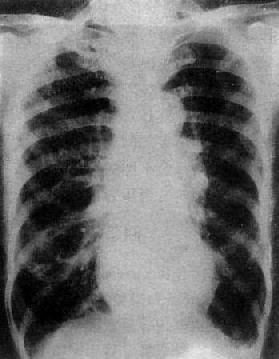

图3-2-15 二尖瓣狭窄

A.右前斜位:右心室增大,肺动脉段突出(↑),心前间隙变窄(↑),左心房轻度增大;B.后前位:心增大,呈二尖瓣型,右心室增大,肺动脉段突出,左心耳增大,出现第三弓(↓),有肺瘀血表现;C.左前斜位:右心室增大,左心房增大不明显;左心室不增大。